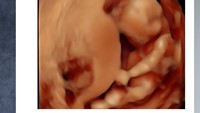

Istri Rigen hamil anak keempat. (Foto: dok Instagram indhningtys)